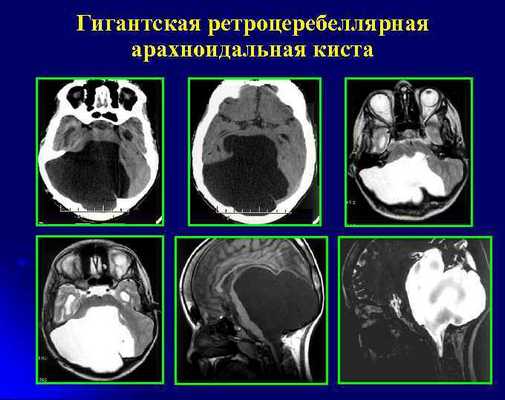

Арахноидальные кисты представляют собой скопление ликвора между листками расщепленной паутинной оболочки. Арахноидальная киста обычно не сопровождается другими мальформациями. Незначительная часть арахноидальных кист имеет приобретенное происхождение - следствие лептоменингита, операции или кровоизлияния. Частота составляет около 1% от внутричерепных образований. Соотношение полов М:Ж, как 4:1. Типичная локализация - средняя черепная ямка (в области Сильвиевой борозды 50%), межполушарная щель, мосто-мозжечковый угол (11%), за скатом или на уровне четверохолмия (10%), в области червя мозжечка (9%), реже в области межножковой и предмостовой цистерн (3%), а также супраселлярной и хиазмальной цистерн. В зависимости от размера предложено делить кисты на 3 типа (Galassi, 2006), что однако, не имеет практического значения. Ретроцеребеллярная арахноидальная киста довольно часто встречаются за мозжечком и отличима от mega cisterna только по неизменённой задней черепной ямке. При МРТ головного мозга содержимое кисты чисто ликворное, стенки гладкие, чётко очерченные, внутри кисты могут быть перегородки. Мелкие арахноидальные кисты очень трудно увидеть при МРТ головного мозга. Меняя ширину окна и его уровень на Т1-зависимых МРТ изображениях можно заметить, что киста чуть светлее ликвора. Дифференциальная диагностика с эпидермальными кистами лучше осуществляется с помощью МРТ последовательности FLAIR. На них при МРТ головного мозга эпидермальные кисты становятся яркими, в отличие от гипоинтенсивных арахноидальных. Вероятно, вариантом арахноидальной кисты является нейроэпителиальная киста, которая при МРТ головного мозга имеет типичное расположение в области хориоидальной щели.